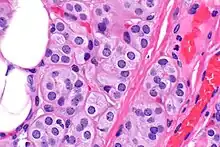

| Microscopic image of a thyroid adenolipoma | |

Adenolipomas are diagnosed by surgical resection and examining the tumor with a microscope.[5] The presence of eccrine sweat glands are used to distinguish the tumor from a common lipoma. Size and the development of the capsule (tissue surrounding the tumor) can also aid in diagnosis. [6]